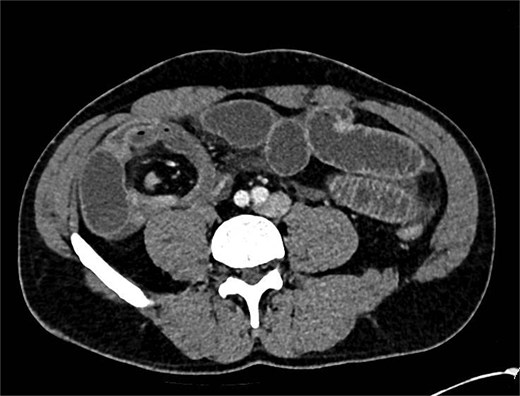

He was taken to theatre for a diagnostic laparoscopy. Intraoperatively, it was noted there was a long, thin ischaemic MD torting around the distal ileum causing obstruction of the proximal small bowel. He underwent adhesiolysis of a band at the tip of the diverticulum (Fig. 3) which then allowed for detorsion of the diverticulum around the terminal ileum (Fig. 4). The MD was subsequently stapled off and excised (Fig. 5). The rest of the small bowel was pink and preinstalling well.

Post-operative histology showed a ‘pouch like structure with single staple line and blind ended measuring 95 mm in length by up to 22 mm in diameter. The serosa appears dusky with microscopic histology confirming early ischaemic change’, which was in keeping with the intra-operative diagnosis.